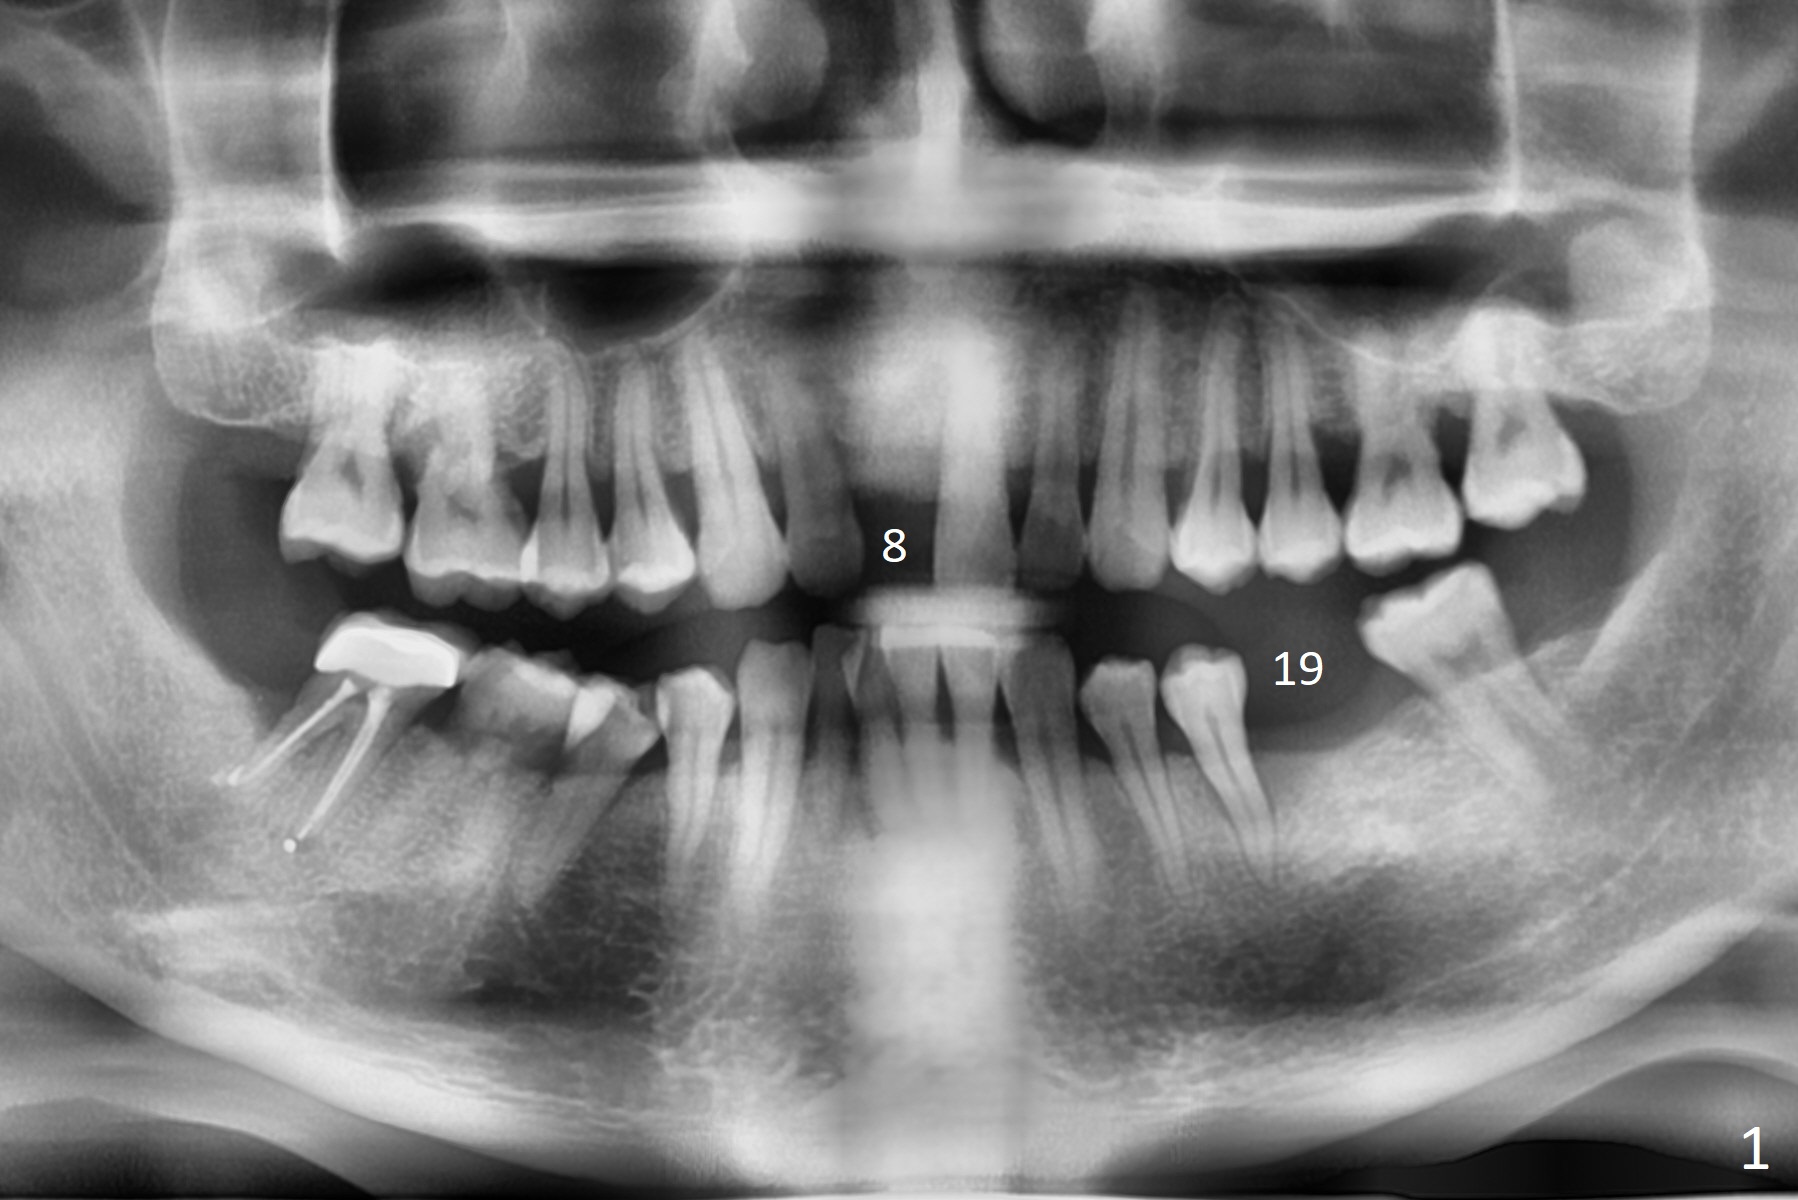

A 50-year-old man loves chewing bone and crab leg. The tooth #19 was extracted due to fracture 1.5 years ago (Fig.1). To reduce abutment screw loosening, IS guide will be used to create osteotomy, while a Tatum implant will be place initially with the guide (Fig.2). There appears no screw loosening associated with Tatum implants. The ridge at #8 is atrophic; a 2.5x10 mm Mini-implant will be placed palatal (Fig.3). The mesiopalatal defect (Fig.4 (lingual view) *) will be bone grafted after implant placement. Incision will be made after the 1st drill for access. The guide will be made with gingival clearance. A piece of 6-month membrane will be cut with a hole buccally to cover the bone graft and slide through the implant.